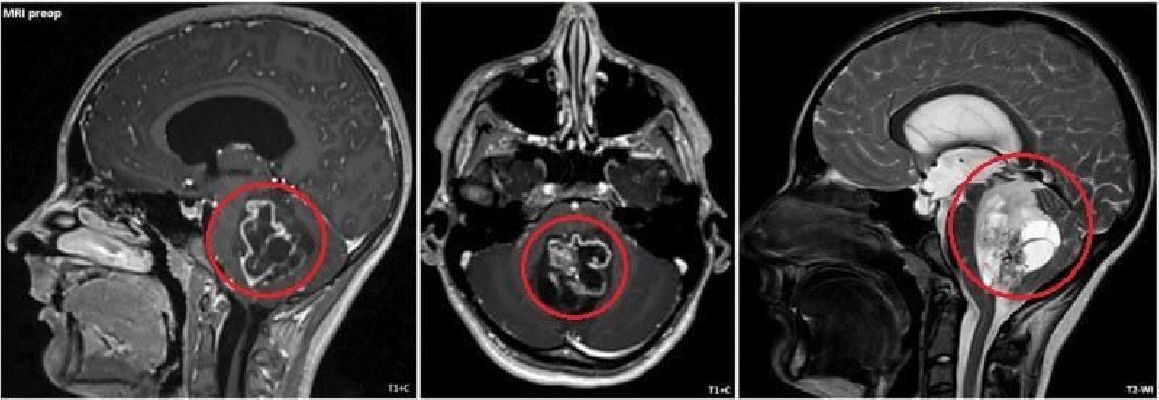

Подросток поступил в больницу с жалобами на постоянную тошноту и рвоту. Обследование показало, что это состояние вызвала опухоль, выросшая в задней черепной ямке.

«Опухоль росла из области, которая отвечает за жизненно важные функции, поэтому любое, даже маленькое повреждение могло привести к тяжёлым неврологическим осложнениям. В ходе операции мы помощью ультразвукового аспиратора смогли аккуратно удалить у пациента опухоль с сохранением критически важных структур головного мозга», — сказал заведующий нейрохирургическим отделением Аслан Текоев.Сейчас прооперированный подросток чувствует себя хорошо. Его уже выписали из больницы.